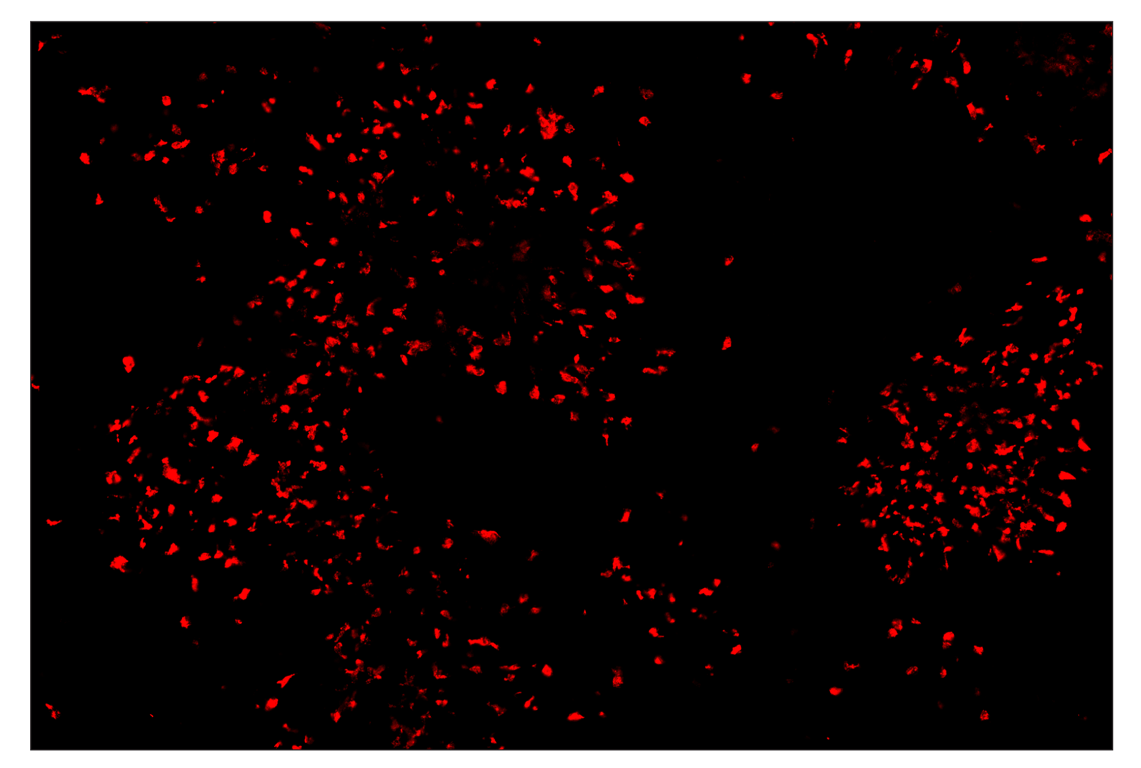

SignalStar™ multiplex immunohistochemical analysis of paraffin-embedded human squamous cell lung adenocarcinoma using Arginase-1 (D4E3M) & CO-0075-647 SignalStar™ Oligo-Antibody Pair #44900 (red). All fluorophores have been assigned a pseudocolor, as indicated. Staining was performed on the BOND RX autostainer by Leica Biosystems.

Immunohistochemistry Image 3: Arginase-1 (D4E3M) & CO-0075-750 SignalStar<sup>™</sup> Oligo-Antibody Pair